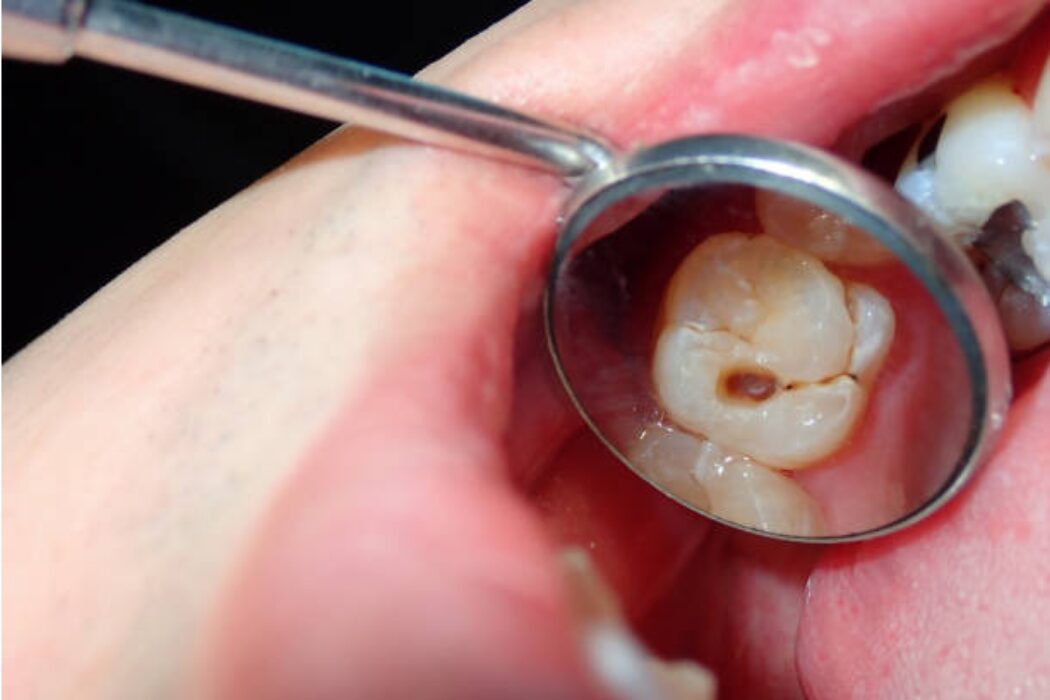

Una caries no tratada puede avanzar desde el esmalte hasta afectar al nervio y provocar infecciones. Detectarla a tiempo permite tratamientos más conservadores y predecibles.